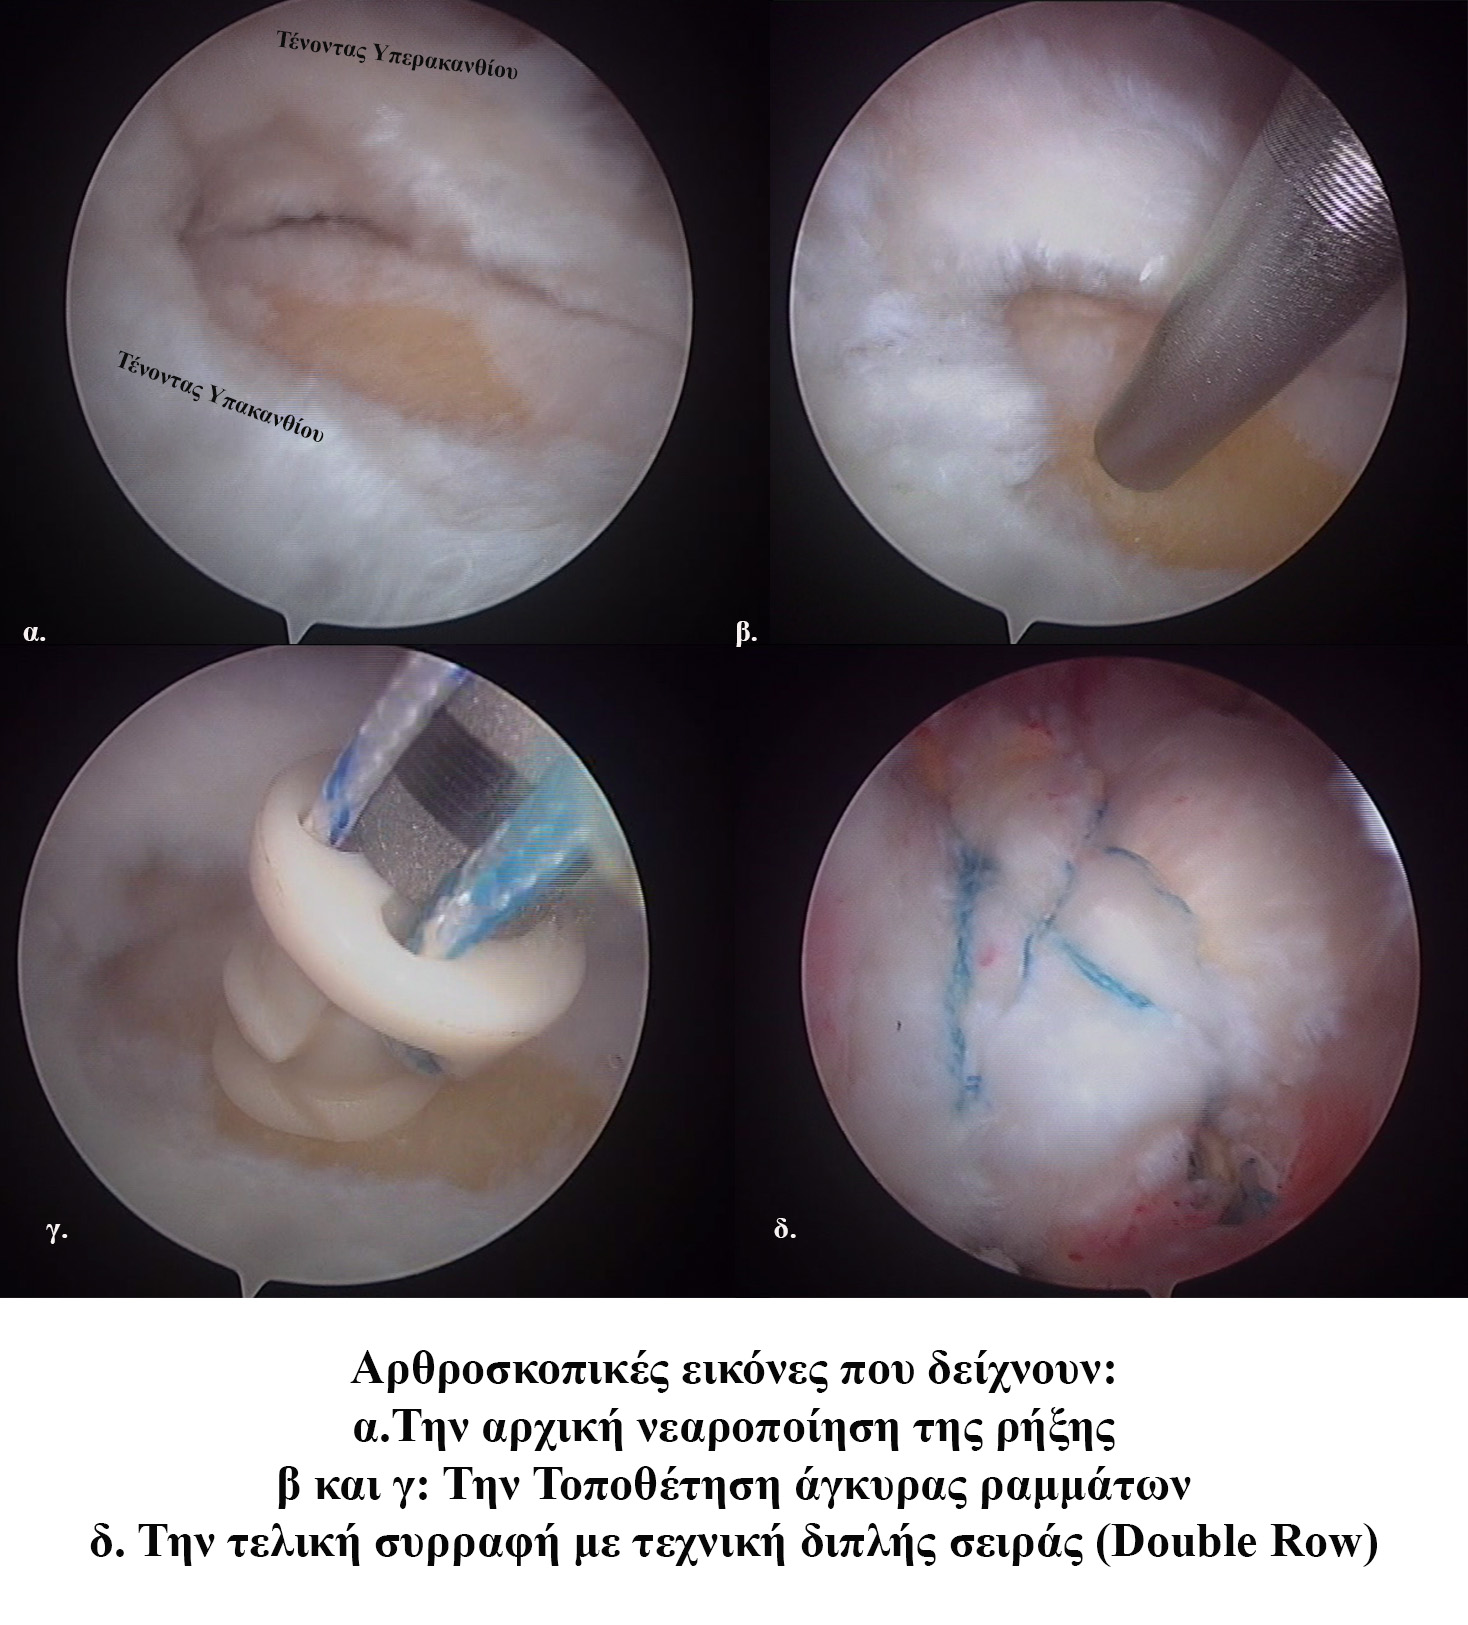

Διαμέσου τομών 5 χιλιοστών και με τη βοήθεια κάμερας υψηλής ανάλυσης πραγματοποιούνται:

-Νεαροποίηση της βλάβης του τένοντα

-Νεαροποίηση του βραχιονίου οστού

-Καθαρισμός του υπακρωμιακού ορογόνου θυλάκου

- Τροποποίηση της μορφολογίας του ακρωμίου, όπου χρειάζεται και μετά από κατάλληλο προεγχειρητικό σχεδιασμό

-Συρραφή και επανακαθήλωση των τενόντων στην κεφαλή του βραχιονίου με τη χρήση βιοαπορροφήσιμων υλικών- αγκυρών